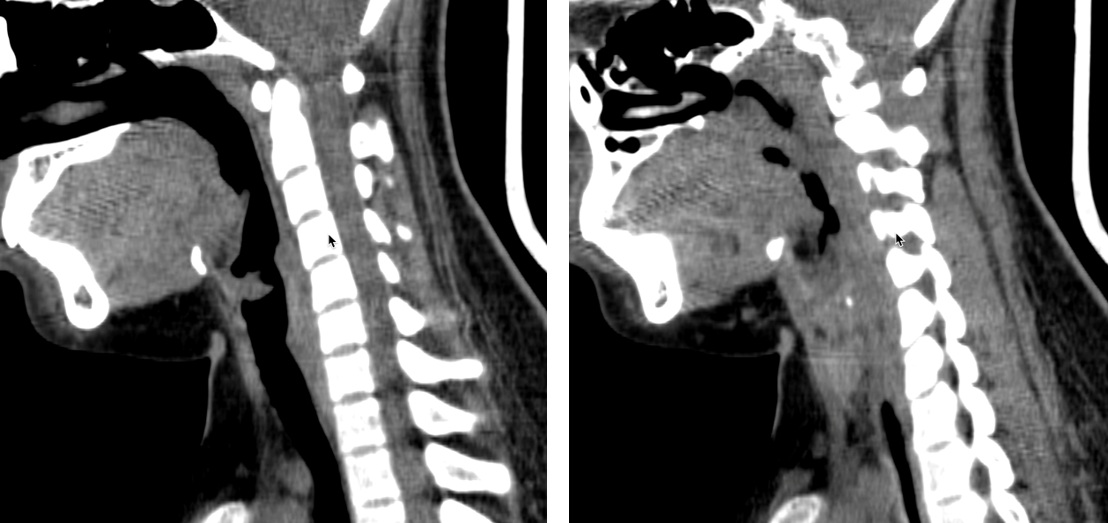

Hình 2. Hình ảnh Papilloma trên CT scan

CT scan: Vị trí dây thành âm có cấu trúc đậm độ mô mềm kt # 9*6mm. hạch cổ nhóm II hai bên đường kính trục ngắn <10mm.